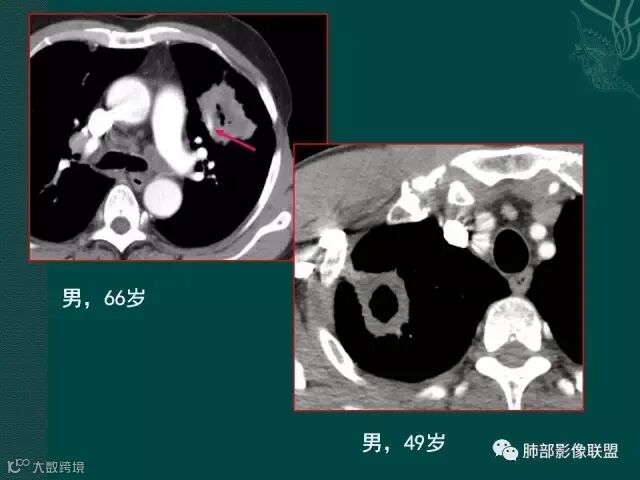

病史似乎是炎性;空洞型病变,靠近纵隔的时候,一定要看对纵隔是否有侵蚀,这是相当重要的。

红箭头所指是右上肺静脉,起始部是完好的,上一层被病变完全包埋,管腔变窄,管壁形态不规则,并侵犯相邻纵隔。

肺癌靠近纵隔时,对纵隔的侵犯,对诊断有重要诊断价值,炎症的话很少会侵犯血管。